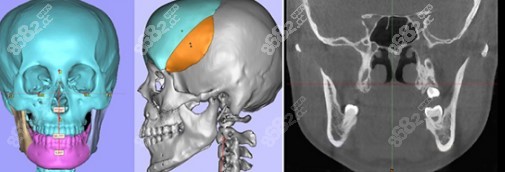

优势1:广州广大医院双鄂手术做的是3D导板双鄂手术,也就是双鄂导航手术,能够提前预知术后样子。

优势2:做的3D打印导板能够更准的定位截骨,包括定位截骨线、截骨范围、去骨量等,不会出现截骨量多的情况,做双鄂手术3年、5年或10年后不会出现脸下垮。

优势5:广大医院双鄂手术中有3D打印咬合板指导上下颌骨移动方向和距离,精细到0.01mm,术后和术前看到的样子一致。